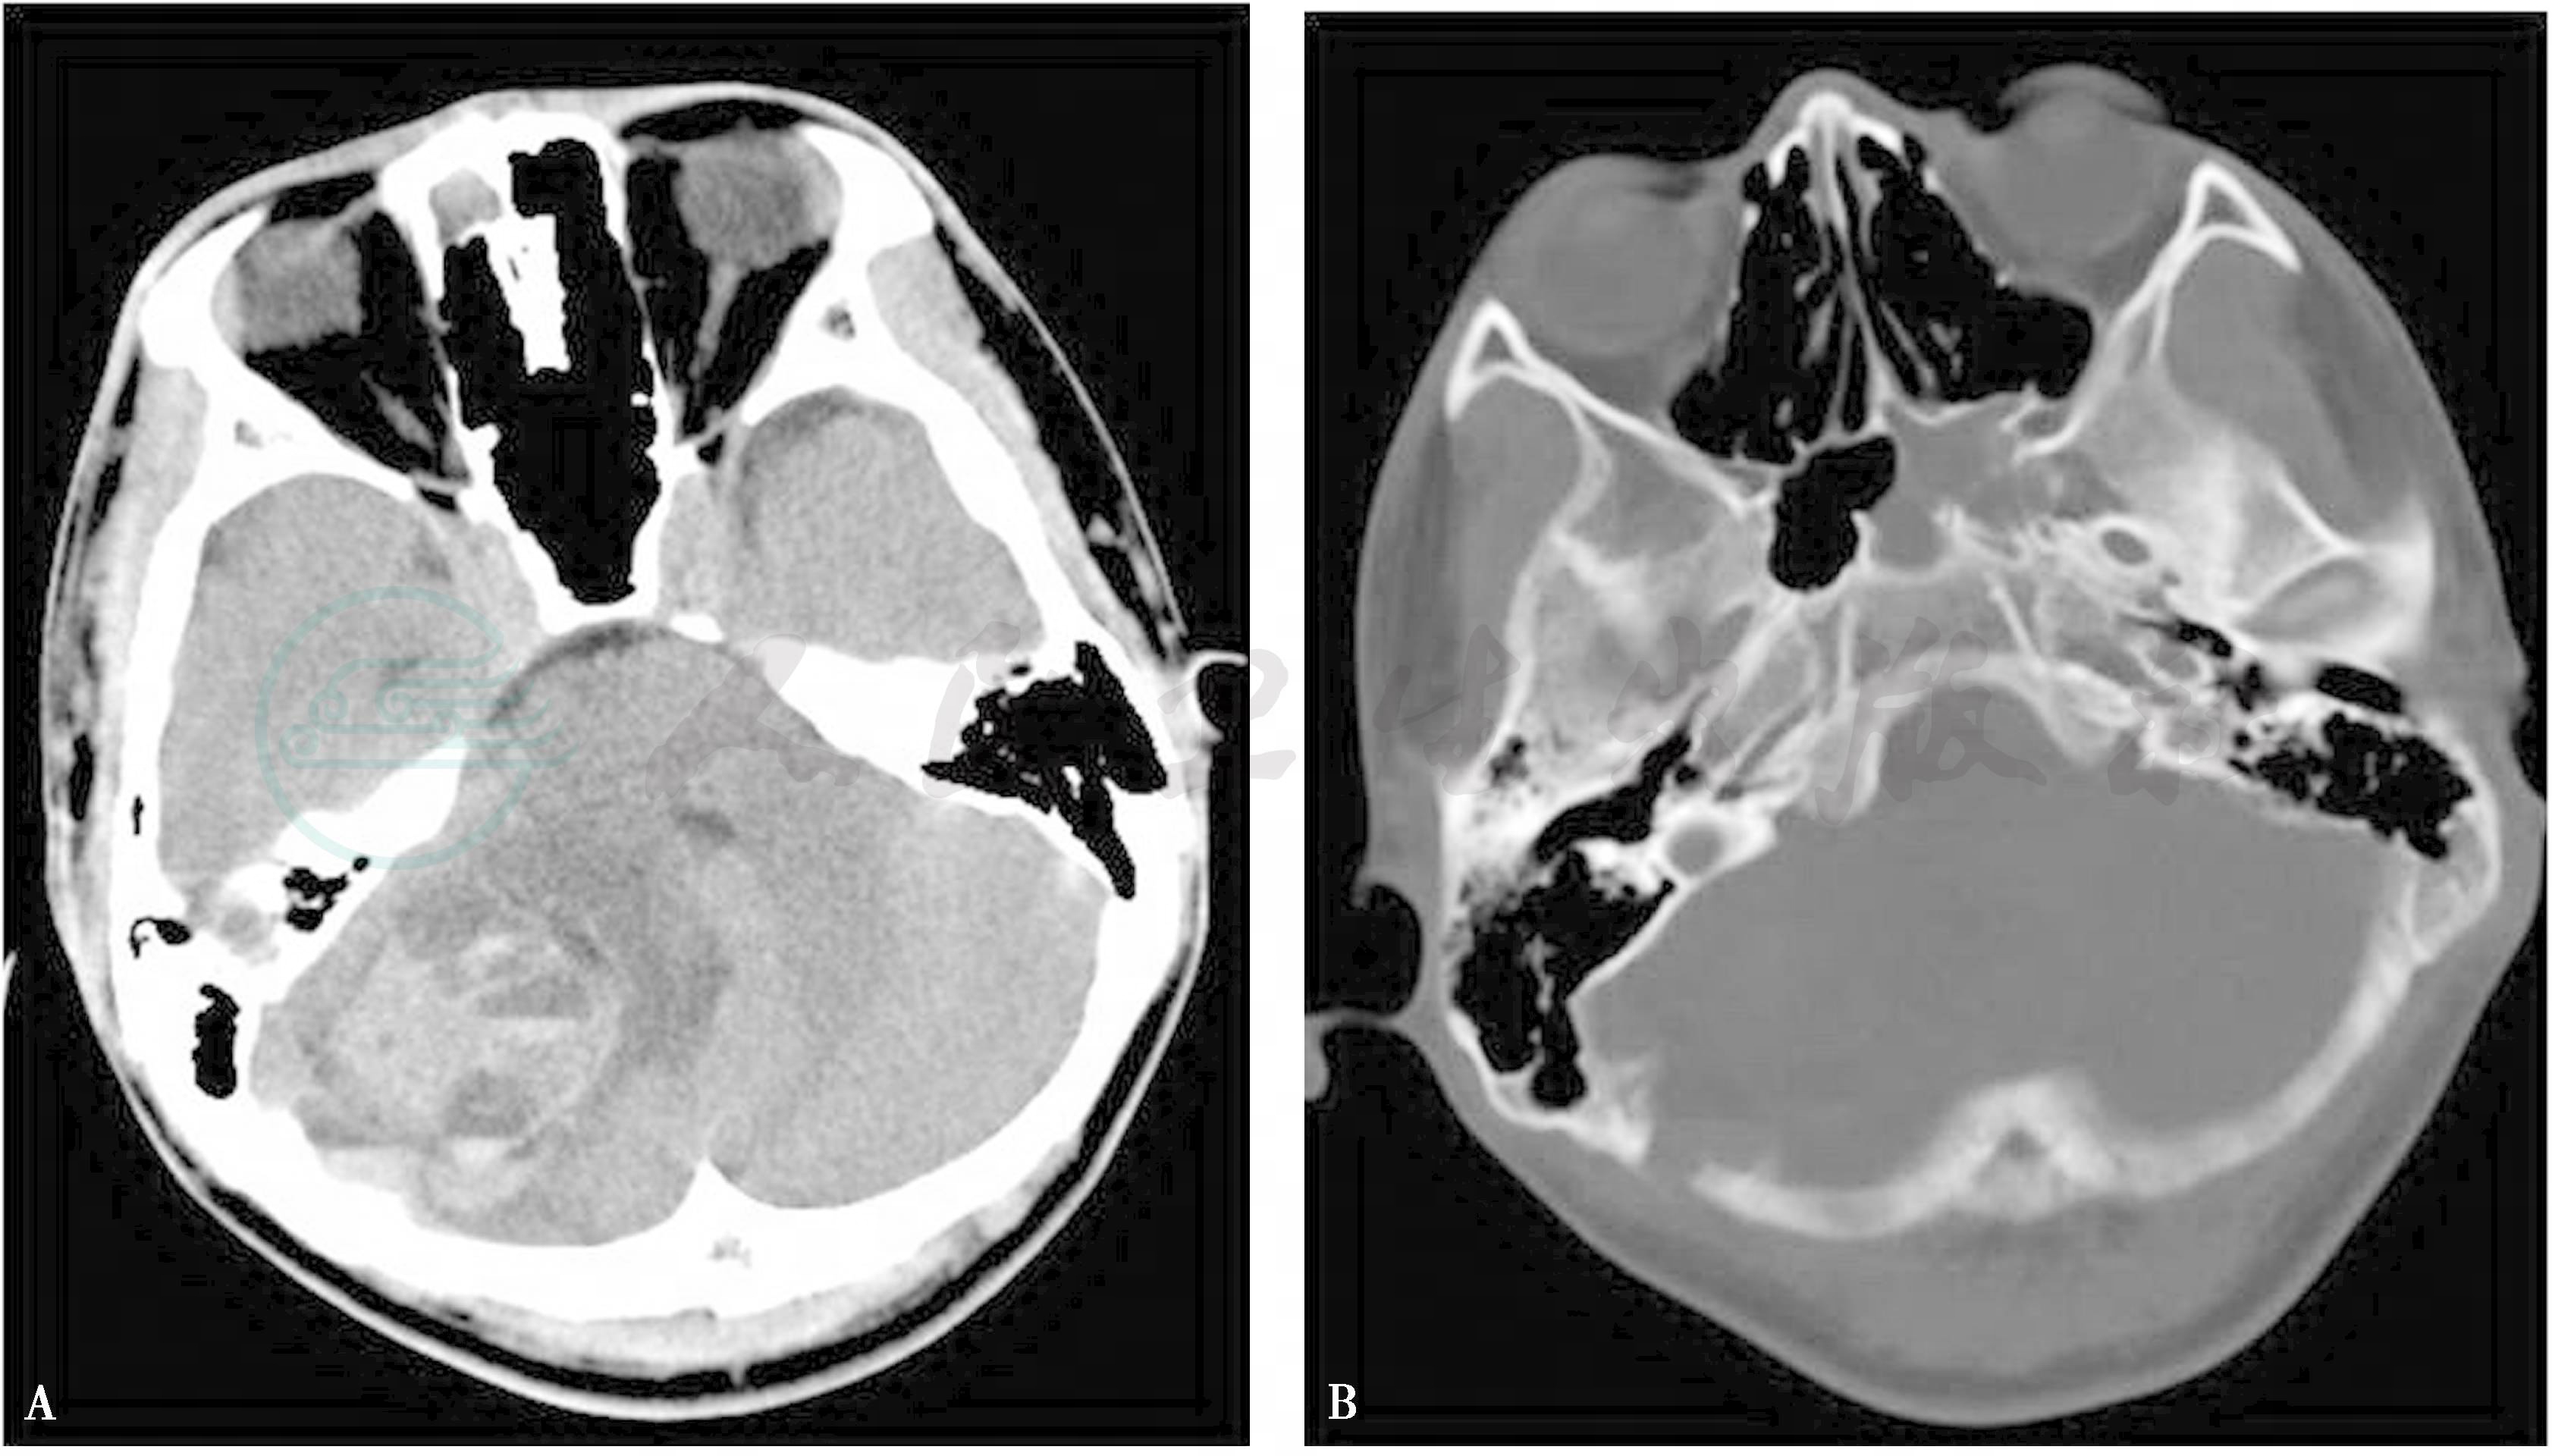

X线、CT表现 颅面骨动脉瘤样骨囊肿多表现为囊状膨胀性透光区,骨皮质变薄如蛋壳样,边界清楚,可见硬化,多无骨膜反应,病灶内有粗细不等的小梁分隔,呈皂泡状、蜂窝状外观。CT扫描显示大小不等的液性密度囊区内可见液-液平面,平面以上为低密度,平面以下为略高密度,是ABC的特征性表现 (图1A、B)。为更好地显示液-液平面,检查前最好让患者在检查床上静卧15~20分钟。增强扫描病变实质部分明显强化,液性囊腔无明显强化。

图1 动脉瘤样囊肿

A、B:CT示右侧颞枕骨交界处见囊状膨胀性病变,边界清楚,局部颅骨内外板膨胀、消失,病灶向颅内延伸形成较大多房状略高密度肿块,内见多个液-液平面,邻近脑组织受压,周围见片状低密度水肿区;C~E:MR扫描显示右侧颞枕部见边界清楚的多囊状肿块影,呈等长T1、等长T2混杂信号,边缘有薄如纸的低信号边界,囊腔大小不一,信号不均,可见液-液平面,液面上部呈明显长T1长T2信号,下部呈等T1等T2信号,病灶周围见条片状长T1长T2水肿影